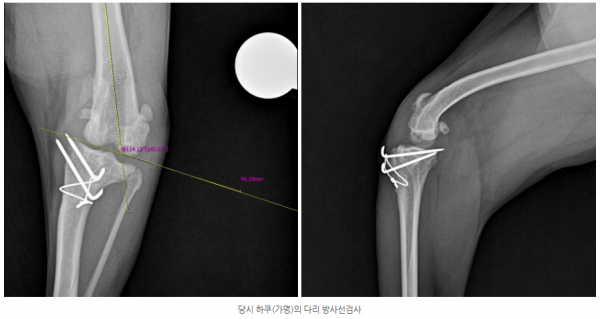

- 좌측 슬관절에서 슬개골 재탈구

- anatomic lateral distal femoral angle (aLDFA) 약 114°로 확인

하쿠(가명)는 고랑성형술과 경골결절변위술·외측 연부조직 봉합술만으로는

교정이 충분하지 않았고 허벅지뼈가 안쪽으로 휘어진 변형까지 확인되어

이를 바로잡는 대퇴골 교정 절골술이 추가로 필요했습니다.